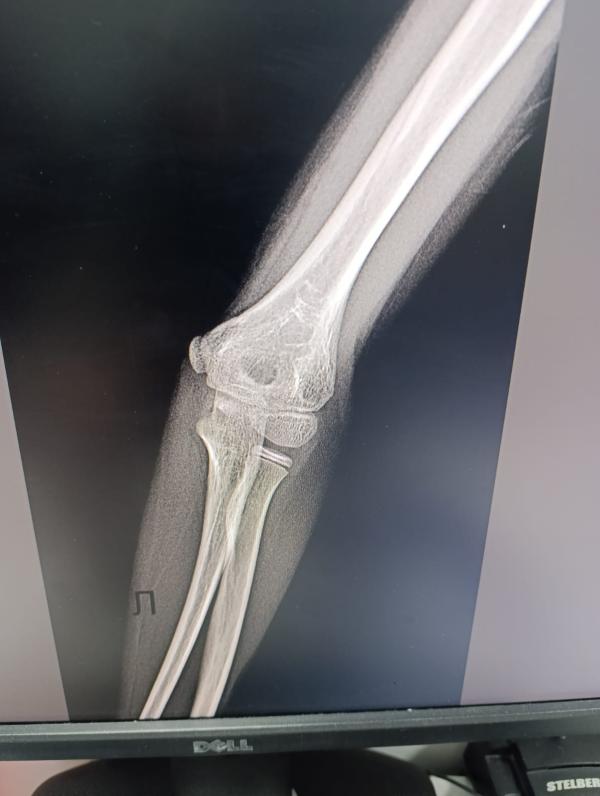

post image 2

Сыну сделали снимок, но врача нет . Врач будет завтра. Может кто увидит и подскажет, есть перелом или что-то такое, или нет.

Сын вчера упал на локоть, жалуется что болит

Трещина и осколок, правильно вам написали

И еще и осколок похоже 🤷🏻‍♀️